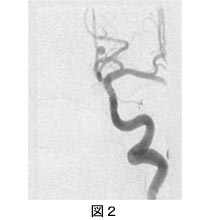

脳動静脈奇形は先天的な病気です。血管が発生するときおのおのが役割を持って発達してくるのですが、毛細血管の部分が正常に分化できないと異常な血管網ができることがあります。これをナイダスと呼びます。動脈からこのナイダスを介して静脈に早い血流が流れていくのがこの病気の本態です。本来、毛細血管を介して細胞への酸素や栄養分の受け渡しを行うのですが、これをしないため圧の高い動脈から壁の薄い静脈に直接に近い形で血液が流れ込みます。このため、何かの影響で静脈側の壁が破綻すると脳内出血を起こすことになります。また、この部分は脳組織にはないものなのでこの場所を起点にてんかん発作を起こすこともあります。50%から60%は脳出血を起こし、30%から40%はてんかん発作を起こすと言われています。CTやMRI検査で診断できますが、治療法を選択するには脳血管撮影が必要となります。脳動静脈奇形は年間2%前後の出血率があり、出血した1年間だけは6%前後に上昇すると言われています。1回の出血による死亡率は10%前後あり、出血による重篤な後遺症を残す可能性も高いと言えます。働き盛りの30台前後の出血発症が多いため、治療のタイミングや治療法の選択をより慎重に選ぶべきと考えています。治療法には脳血管内治療、開頭術、放射線治療(ガンマナイフ、サイバーナイフ)があります。脳動静脈奇形の重傷度によっては単独の治療法で治せるものもありますが、各々の組み合わせで治療する場合もあります。脳血管内治療は脳動静脈奇形の異常血管網の近傍に非常に細いカテーテルを挿入して、液体塞栓物質を用いて行います。大きなナイダスを持った脳動静脈奇形や多数の流入動脈を持っているものに関して段階的にナイダスを小さくしたり、流入動脈の本数を減らしたりします。こうすることで、放射線治療の効果を高めたり、開頭摘出術の手助けをしたりします。最近では、小さなものは塞栓術で根治を目指し、大きなものはできるだけ塞栓してから手術、ガンマナイフで根治を目指します。非接着性液体塞栓物質ONYX導入後、治療の安全性、有効性がさらに向上しています。【症例1】 32歳、女性、出産1ヶ月後に小脳出血で発症。小脳虫部に脳動静脈奇形を認めた。NBCA(n-butyl cyanoacrylate 接着性液体塞栓物質)を用いて超選択的に流入動脈から塞栓。脳動静脈奇形は完全に塞栓され、現在まで8年間の間再発を認めていない。